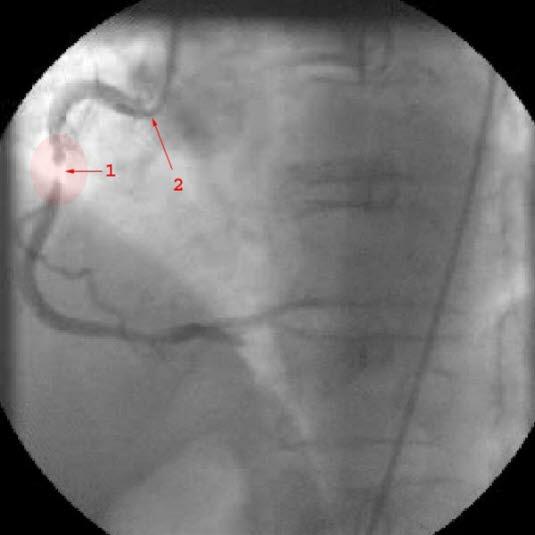

Dette er det vanligste inngrepet, og det minst omfattende. Inngrepet gjennomføres ved at legene fører inn et lite kateter (en plastslange) i en blodåre i lysken eller ved håndleddet. Denne slangen føres så via hovedpulsåren til hjertet, hvor kateteret føres inn i koronararteriene. Ved hjelp av røntgengjennomlysning og kontrastinnsprøyting finner legene de områdene av koronararteriene som er forsnevret eller blokkert. På kateterspissen befinner det seg en ballong som blåses opp i det trange partiet, og dermed utvides passasjen, og blodstrømmen forbedres. Som regel blir det også satt inn en forsterkning i det tidligere trange partiet i blodåren, en spiralformet netting som på fagspråket kaller en "stent". Stenten øker sjansen for at blodåren forblir åpen. Dette inngrepet kan gjøres i lokalbedøvelse, og med forberedelser og etterbehandling tar inngrepet noen få timer.